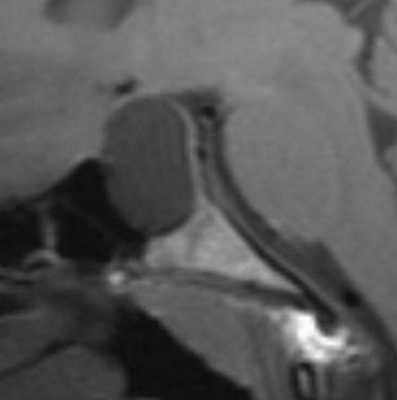

Киста кармана Ратке представляет собой редко встречающееся образование из остатков эмбриональной эктодермы (щель Ратке), расположенное между долями гипофиза. Выявляется в любом возрасте, но чаще в 50-60 лет. Клинические проявления связаны с масс-эффектом. При МРТ головного мозга выявляется небольшая (3-5мм) киста с четким контуром, без отека вокруг, однородная по структуре. Сигнал на МРТ головного мозга зависит от содержимого. При серозном содержимом сигнал типично жидкостный, при мукоидном киста светлая на Т1-взвешенных МРТ головного мозга. В 70-80% случаев внутри кисты выявляется неконирастирующийся узелок («пятно») - признак патогномоничный для кисты кармана Ратке. В редких случаях киста достигает больших размеров и даже выходит за пределы седла. Стенка кисты иногда усиливается при МРТ головного мозга с контрастированием. Дифференциальная диагностика при МРТ головного мозга должна проводиться с арахноидадьной и эпидермоидной кистами, тератомой, кистозной аденомой гипофиза и краниофарингиомой. Иногда при МРТ головного мозга киста кармана Ратке напоминает “пустое” турецкое седло. При маленьких размерах кисты ее на до дифференцировать на МРТ с микроаденомой гипофиза.